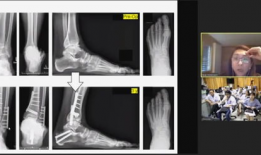

亲爱的读者们,你是否曾因为关节疼痛而烦恼不已?又或者,你身边有没有朋友正在经历骨科疾病的困扰?今天,就让我带你走进一个全新的世界...